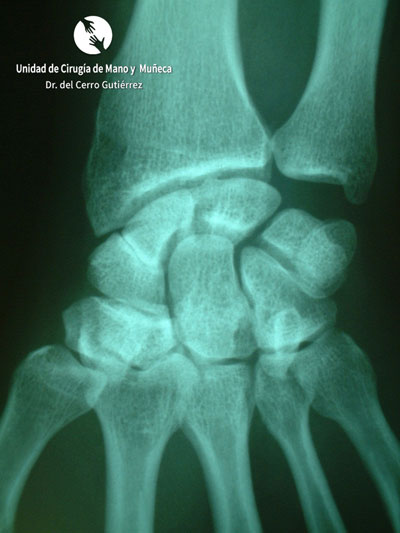

Fractura del Escafoides